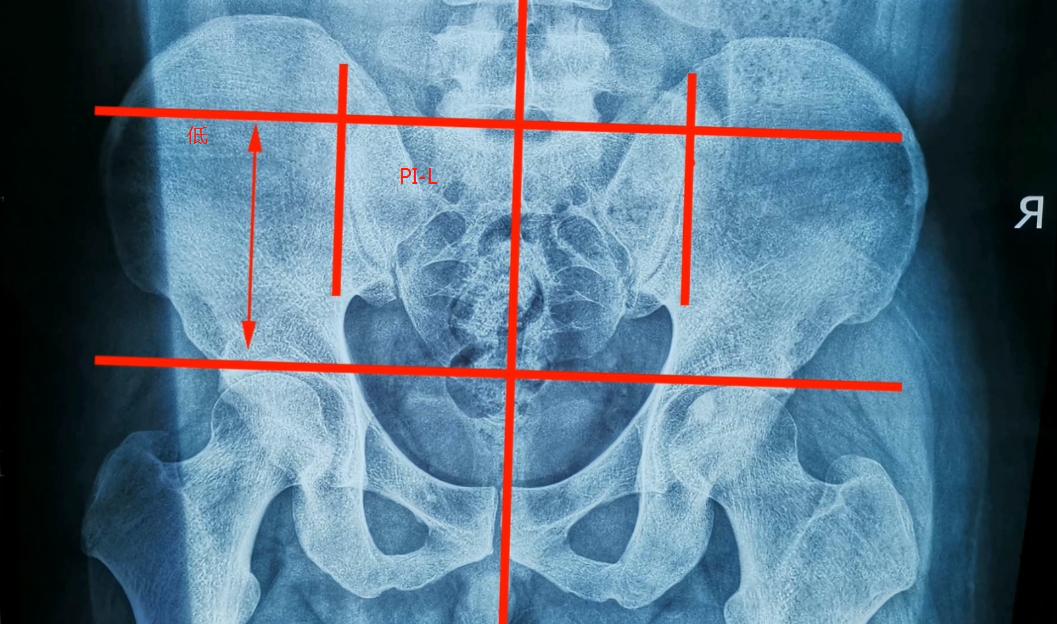

首先以两侧股骨的顶点画出基准线,然后再以骶骨第二骶椎划出垂直线,

通过之前的学习,我们发现图中的垂直线位于整个耻骨联合的右侧,

说明右侧髂骨发生了EX偏位,左侧髂骨是IN偏位(如果有不明白的地方可以分翻阅我们之前的视频再去做一下回顾)

接下来以骶骨最外侧两个点做标记,然后画出垂直线,测量骶骨中线与两侧垂直线各自的距离

如果两个距离不相等那么就说明的骶骨存在左右旋转问题,旋转方向是窄的一侧

我们可以在图中做下标注

通常有两种方式

宽的一侧可以标记为PL或LP,代表左侧(L)向后(P)偏位

窄的一侧标记为RE或ER,代表右侧(R)向外(E)偏位

宽侧标注方式LP

窄侧标注方式RE

以骶骨的上关节突旁的两个沟做延长线,观察它与股骨的基准线是否是平行,

如果出现不平衡,以左侧为例,左侧低右侧高的话,说明左侧不仅仅有向后偏位而且存在向下偏位,我们可以标注PI-L或L-PI